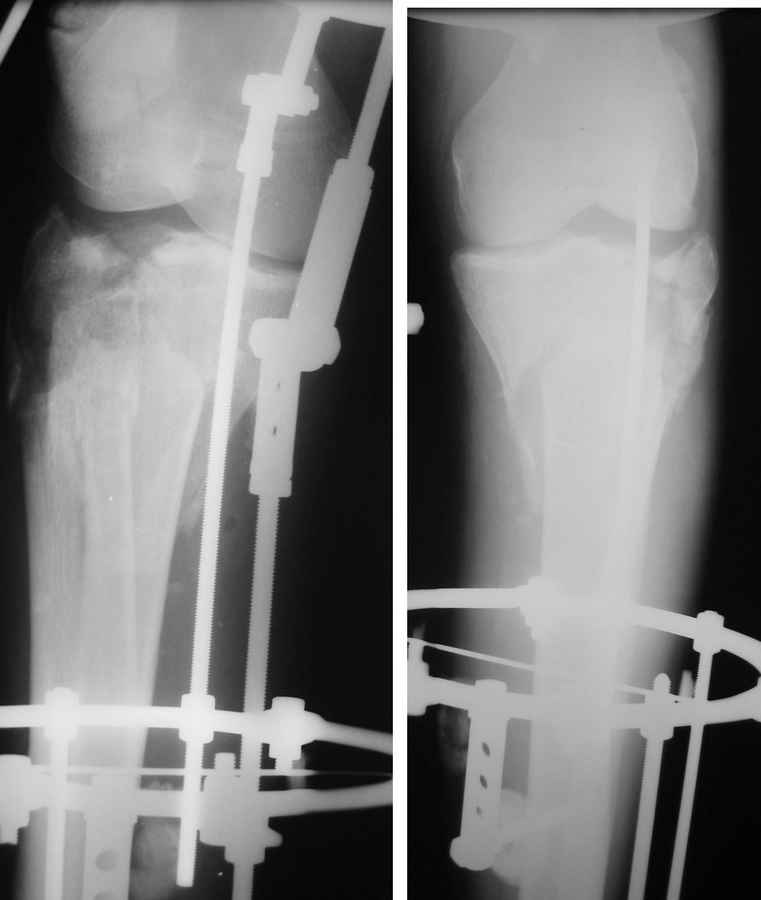

Состояние мягких тканей оказалось принципиальным в разработке плана операции.

Очаг некроза 4 на 5 см по передней поверхности голени не оставил никакого варианта кроме внешнего остеосинтеза.

Но решили делать в 2 этапа. Первый - восстановить ось и дать костной крошке в проксимальном отделе консолидироваться.

Второй - собственно артродез.

Но по результатам первого этапа думаем дать пациенту попользоваться ногой. А там посмотрим.